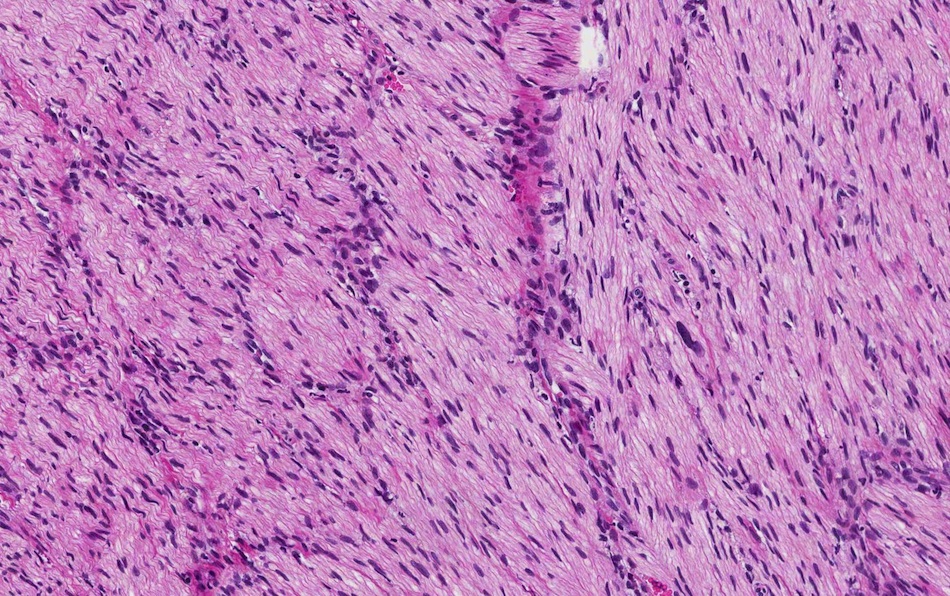

Microscopic images:

Both cases showed disorganized and thickened nerve bundles composed of spindle shaped cells, without atypia. Case A also showed a focal foreign body type giant cell reaction adjacent to the disorganized nerve bundles and a strongly immunoreactive S100 stain.

Histology typically shows hyperplastic nerve bundles, positive for S100.

Microscopic images:

Both cases showed disorganized and thickened nerve bundles composed of spindle shaped cells, without atypia. Case A also showed a focal foreign body type giant cell reaction adjacent to the disorganized nerve bundles and a strongly immunoreactive S100 stain.

Histology typically shows hyperplastic nerve bundles, positive for S100.